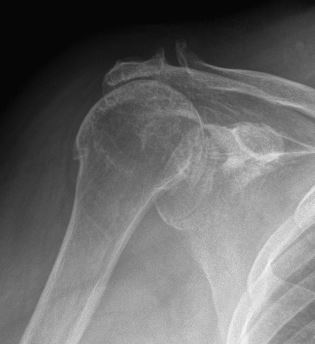

Non-United Fracture of Proximal Humerus

Cuff Tear Arthropathy